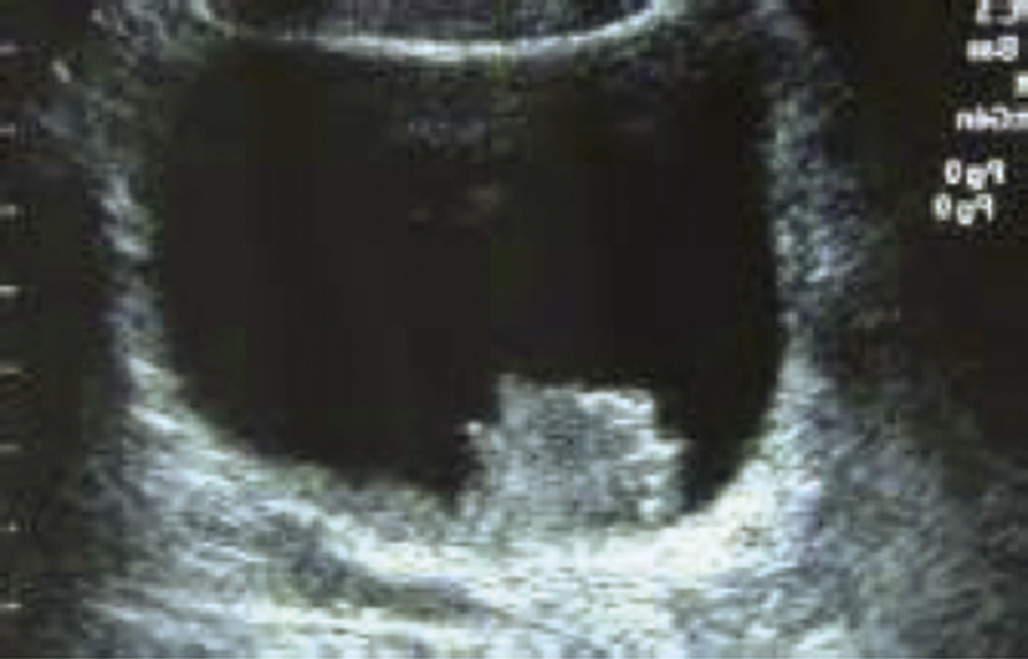

Échographie vésicale par voie sus-pubienne

Réalisée vessie en réplétion, elle a une bonne sensibilité pour les tumeurs de vessie dont la taille est supérieure à 5 mm (sensibilité : 84 %). Elle permet également d’explorer un éventuel retentissement sur le haut appareil (dilatation des cavités pyélo- calicielles) pouvant traduire une infiltration du muscle vésical ou une localisation au niveau du trigone avec envahissement du méat urétéral correspondant.

Elle reste cependant dépendante de l’opérateur et de la morphologie du patient (peu échogène si obèse), et est de moins en moins réalisée depuis l’avènement de l’uro-tomodensitométrie (uro-TDM).